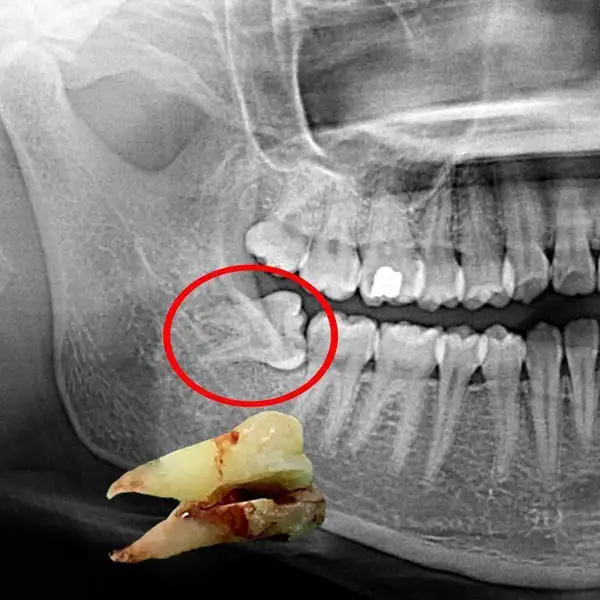

1. Dental Checkup with Digital X-Ray

A comprehensive oral examination to assess teeth, gums, bite, and overall oral health. Using advanced digital X-rays, hidden problems such as cavities, infections, bone loss, and impacted teeth can be detected at a very early stage — even before symptoms appear.

Early diagnosis allows for timely and minimally invasive treatment, helping prevent pain, complications, and costly dental procedures in the future. Regular dental checkups play a vital role in maintaining a healthy smile and overall well-being.

12. Tooth Extraction(Including Wisdom Teeth)

Safe and comfort-focused removal of damaged, decayed, loose, or impacted teeth using modern techniques and advanced anesthesia. Includes simple and surgical extractions such as wisdom tooth removal when required.

Our gentle approach ensures minimal discomfort during the procedure, faster healing, and smooth recovery. Detailed post-extraction care instructions are provided to promote proper healing and prevent complications, helping you return to normal activities quickly and comfortably.